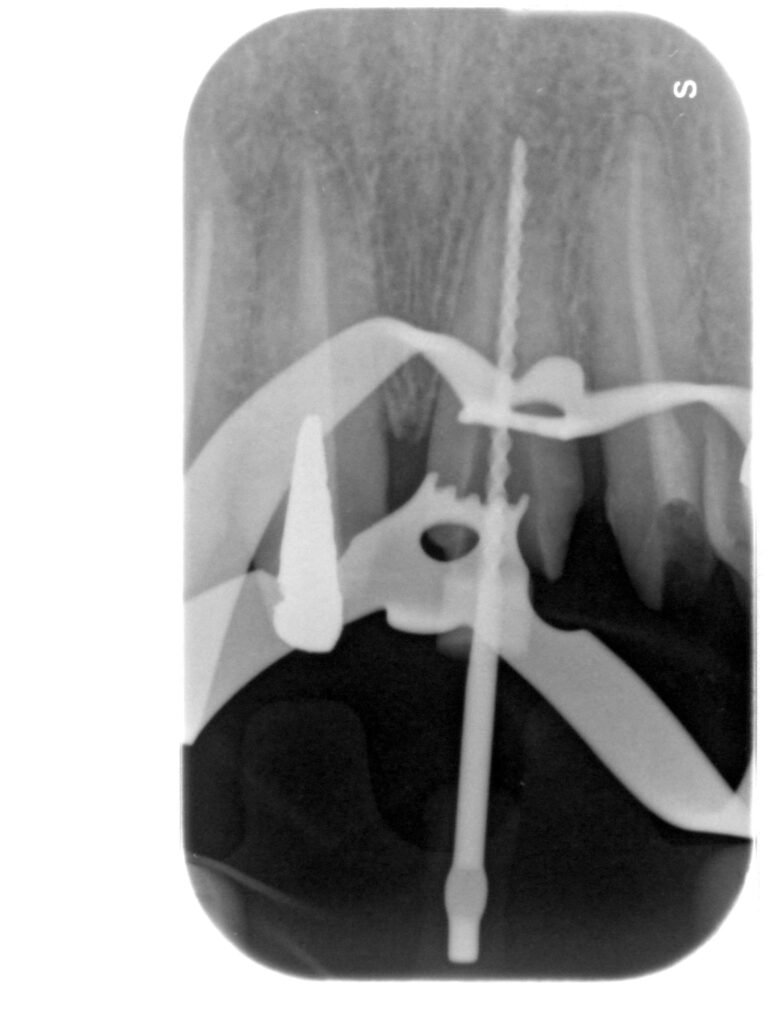

Caso clinico – ritrattamento ortogrado con apical plug in MTA